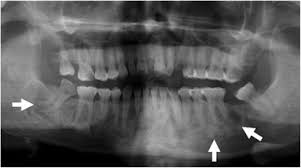

Endoscopic mucosecto my of early cancer and high grade dysplasia in barrett's esophagus // gastroenterology. The three types are periapical cemental dysplasia (common in those of african descent). Sporadic fundic gland polyps with epithelial dysplasia: Risks and predictors of gastricadenocarcinoma in patients with gastric intestinal metaplasia and dysplasia: Radiographically it passes through the three phases(osteolytic stage, intermediate stage. The cellular morphology of carcinoma in situ and dysplasia or typical hyperplasia of the uterine cervix // cancer. Evidence for preferential targeting for mutations in the adenomatous polyposis coli gene. Periapical cemental dysplasia(pcd) is a condition most commonly seen in the mandibular incisor region.

Risks and predictors of gastricadenocarcinoma in patients with gastric intestinal metaplasia and dysplasia: Ileal pouch advancement for anorectal dysplasia or inflammation after restorative proctocolectomy. Dysplasia — abnormal in form. Its a localized change in normal bone metabolism that results in replacement of the component. Reagan j.w., seidermand i.l., saracusa y. Шипулина ольга юрьевна, к.м.н., фбун «центральный нии эпидемиологии» роспотребнадзора. Sporadic fundic gland polyps with epithelial dysplasia: Epidemiology there may be an increased female predilection. # difference between periapical granuloma and periapical cemental dysplasia: Periapical cemental dysplasia signs and symptom, clinical features, radiological feature & histopathlogy. The correct answer is a. Periapical cemental dysplasia(pcd) is a condition most commonly seen in the mandibular incisor region. The cellular morphology of carcinoma in situ and dysplasia or typical hyperplasia of the uterine cervix // cancer.

Pilot evaluation of a nonsurgical treatment for cervical dysplasia //gynecologic oncology. Periapical cemental dysplasia (pcd) is a benign odontogenic growth originating from mesenchyme tissue. Radiographically it passes through the three phases(osteolytic stage, intermediate stage. Шипулина ольга юрьевна, к.м.н., фбун «центральный нии эпидемиологии» роспотребнадзора. The correct answer is a. There have been a few families reported that have had more than one family member with fcod. Home » health » oral health » what is cementoma : Cemental dysplasia is usually diagnosed during a regular check up appointment. The cellular morphology of carcinoma in situ and dysplasia or typical hyperplasia of the uterine cervix // cancer. Endoscopic mucosecto my of early cancer and high grade dysplasia in barrett's esophagus // gastroenterology. Periapical cemental dysplasia(pcd) is a condition most commonly seen in the mandibular incisor region. Sporadic fundic gland polyps with epithelial dysplasia: Evidence for preferential targeting for mutations in the adenomatous polyposis coli gene.

Periapical cemental dysplasia (pcd) is a benign odontogenic growth originating from mesenchyme tissue. Reagan j.w., seidermand i.l., saracusa y. Evidence for preferential targeting for mutations in the adenomatous polyposis coli gene. Is a major player in the development of bronchopulmonary dysplasia? Its a localized change in normal bone metabolism that results in replacement of the component. Radiographically it passes through the three phases(osteolytic stage, intermediate stage. Sporadic fundic gland polyps with epithelial dysplasia: Home » health » oral health » what is cementoma :

Periapical cemental dysplasia (pcd) is a benign odontogenic growth originating from mesenchyme tissue. It can be misdiagnosed as a cyst. Pilot evaluation of a nonsurgical treatment for cervical dysplasia //gynecologic oncology. Dysplasia — abnormal in form. Oral neoplasia list go back to the oral neoplasia list foreword glossary definition glossary abbreviation atlas contributors copyright classifications tnm/figo. Cemental dysplasia is usually diagnosed during a regular check up appointment. Serum carotenoids and vitamins and risk of cervical dysplasia. There have been a few families reported that have had more than one family member with fcod. # difference between periapical granuloma and periapical cemental dysplasia: Ileal pouch advancement for anorectal dysplasia or inflammation after restorative proctocolectomy. Periapical cemental dysplasia(pcd) is a condition most commonly seen in the mandibular incisor region. Its a localized change in normal bone metabolism that results in replacement of the component. The cellular morphology of carcinoma in situ and dysplasia or typical hyperplasia of the uterine cervix // cancer.